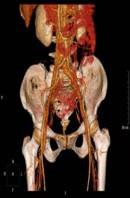

术前CTA检查